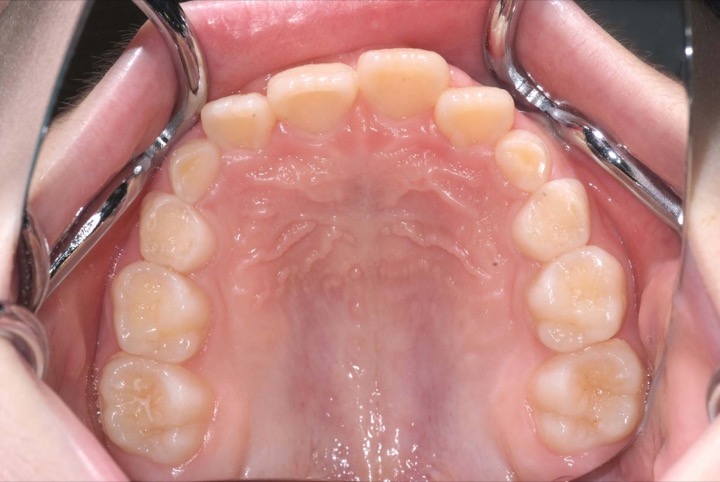

初診時年齢9才の女子で上下顎前歯の部の乱ぐいを気にして来院されました。

検査の結果、叢生と過蓋咬合を伴うアングルⅠ級不正咬合と診断しました。